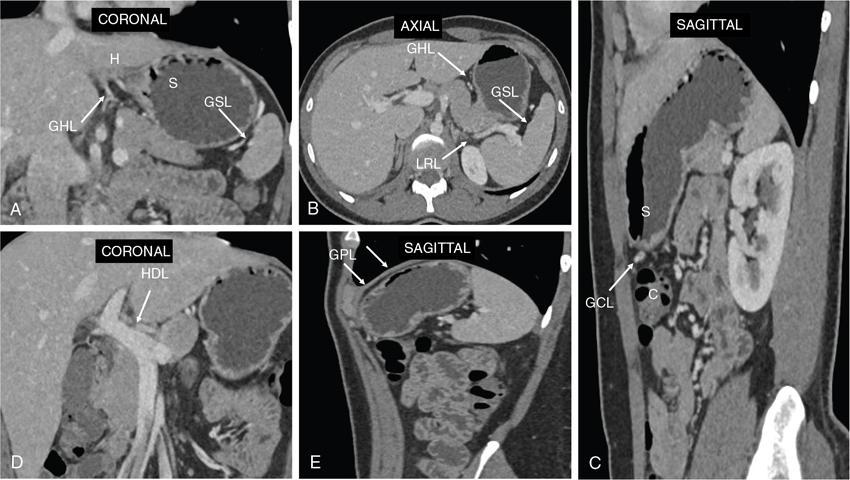

Swarup Nellore, Soumil Vyas, Ujwal Bhure, Ankit Jain, Richa Kothari, Daksh Mehta, Divya Kantesaria, Disha Lokhandwala, Karthik Ganesan The stomach is the most dilated portion of the gastrointestinal tract positioned between the oesophagus and the small intestine occupying the epigastrium, left hypochondrium and umbilical regions of the abdomen performing a multitude of functions including storage and mixing of food and controlling the passage of food into the intestine. Anatomically, the stomach is divided into the following parts (Fig. 8.2.1): the gastric cardia is the portion immediately adjoining the oesophageal opening into the stomach. The fundus is the dome-shaped part above the horizontal plane of the cardiac orifice which undergoes receptive relaxation and is the site of the autonomic pacemaker. The body is the largest part of the stomach extending from the cardiac orifice to the level of incisura angularis (notch like bend in the mid lesser curvature) containing majority of parietal cells (which secrete hydrochloric acid), chief cells (pepsinogen) and enterochromaffin-like cells (ECL). The pylorus is the tubular distal portion of the stomach which is further divided into the gastric antrum and pyloric canal. The pyloric antrum containing G-cells producing gastrin extends from the incisura angularis up to the pyloric sphincter which is an anatomical sphincter formed by concentric thickening of the circular muscle coat and encircles the narrow-slit like pyloric canal. The left dome of diaphragm and oesophagus lie superior to the stomach while the greater omentum and pancreas lie inferiorly. Spleen and liver lie on either side laterally while the transverse mesocolon is located inferolaterally. Diaphragm, greater omentum, left lobe of liver and anterior abdominal wall are anteriorly related to the stomach and contents of lesser sac including pancreas, spleen, splenic artery, transverse mesocolon, left kidney and adrenal gland lie posteriorly. The stomach is embryologically derived from the primitive foregut and is suspended anteriorly by the ventral mesogastrium and posteriorly by the dorsal mesogastrium. During development as the stomach rotates, the peritoneum grows and condenses to form perigastric ligaments, which contain blood vessels, lymphatics, lymph nodes, nerves and fat. The liver forms in the ventral mesogastrium, which develops into the falciform ligament, gastrohepatic ligament (GHL) and hepatoduodenal ligament (HDL). The spleen and pancreas form within the dorsal mesogastrium, which fuses with the posterior abdominal wall to form the gastrocolic ligament (GCL), gastrosplenic ligament (GSL) and splenorenal ligament (SRL). The perigastric ligaments are identified anatomically by the vessels contained in them (Fig. 8.2.2). The gastric cardia and lesser curvature of the stomach are attached to the inferior surface of liver by the lesser omentum by the gastrohepatic ligament respectively which contains the left and right gastric vessels. The inferior free edge of the gastrohepatic ligament extends inferiorly as the hepatoduodenal ligament between the porta hepatis and proximal duodenum gastrophrenic ligament extends between the stomach and the left hemidiaphragm. The gastrocolic ligament identified by the left and right gastroepiploic vessels, connects the greater curvature of the stomach to the anterior surface of the transverse colon. This ligament extends inferiorly as the greater omentum which is a double-layered peritoneum forming a drape anterior to the bowel loops. The gastrosplenic/lienogastric ligament bridges the posterolateral wall of the fundus and greater curvature along the proximal body of the stomach to the splenic hilum and contains the short gastric vessels. The gastrosplenic ligament is contiguous with the lienorenal ligament and both these structures constitute the lateral boundary of the lesser sac. Macroscopically the stomach shows a thick vascular mucosal lining in the form of longitudinal folds called gastric rugae. Microscopic layers of the stomach include mucosa, submucosa, muscularis externa and serosa. The mucosa includes surface mucus cells with simple columnar epithelium, gastric pits, gastric glands, lamina propria and muscularis mucosa. Submucosa includes connective tissue with submucosal Meissner’s plexus. Muscularis externa comprises three smooth muscle layers (longitudinal, circular and oblique) and Auerbach myenteric plexus. The outermost layer called serosa consists of loose connective tissue and visceral peritoneal lining. The arterial supply of stomach is constituted by the branches of celiac artery predominantly in the form of two anastomotic arcades along the lesser and greater curvature. Left gastric artery, a direct branch of the celiac trunk supplies the upper part of the lesser curvature while the lower part is supplied by the right gastric branch of the common hepatic artery arising at the upper border of pylorus. The left gastroepiploic artery, a branch of splenic artery, supplies the upper part of greater curvature and the inferior portion is supplied by the right gastroepiploic artery which is a branch of the gastroduodenal artery. The fundus additionally receives few small short gastric branches from the splenic artery. The veins follow the arteries in their nomenclature. Left and right gastric vein show direct drainage into the portal vein. The splenic vein derives flow from the short gastric and left gastroepiploic vein whereas the right gastroepiploic vein drains into the superior mesenteric vein. Pylorus can be surgically delineated by the prepyloric vein of Mayo lying on its anterior surface. Intrinsic nerve supply consists of the myenteric plexus of Auerbach and submucosal plexus of Meissner. Extrinsic nerve supply consists of sympathetic and parasympathetic components. Sympathetic nerve supply arises from T5 to T9 spinal cord segments supplying the celiac plexus via the greater splanchnic nerve. The plexuses then travel along the respective branches of celiac artery supplying the stomach. Parasympathetic nerve supply is derived from oesophageal plexus of vagus dividing into two vagal trunks. Right (posterior) vagus gives off the posterior gastric branch also called the criminal nerve of Grassi supplying the cardia and fundus of stomach. Right vagus then gives off a celiac branch and continues along lesser curvature of stomach as the posterior gastric nerve of Latarjet supplying the antrum, body and pylorus. Left (anterior) vagus gives off a hepatic branch then continues along the lesser curvature as the anterior nerve of Latarjet supplying the antrum, body and pylorus. Crow’s feet innervation to antropyloric area are important surgical landmarks preserved during highly selective vagotomy receiving branches from both major nerve trunks (anterior and posterior) at the incisura angularis. Anatomical lymphatic drainage is divided into three areas. Area I is the superior two-thirds of stomach draining via the nodes along left and right gastric vessels into the aortic nodes. Area II includes the right two-thirds of the inferior one-third which drains through the nodes along right gastroepiploic vessels via the subpyloric nodes into aortic nodes. Area III includes left one-third of greater curvature draining via short gastric and splenic nodes into suprapancreatic nodes and ultimately into aortic nodes. Gastric lymph node stations are divided into 4 levels with 16 lymph node stations: Paraesophageal nodes below the diaphragmatic hiatus (17) and above the diaphragmatic hiatus (18) are also included. The stomach first appears as a fusiform dilatation in the distal endodermal foregut in the 4th week of embryonic life. The dorsal and ventral mesogastrium suspend the developing stomach to the respective abdominal walls. Preferential growth along the dorsal border of the developing stomach leads to the formation of a convex dorsal border (greater curvature) and a concave ventral border (lesser curvature). The stomach subsequently undergoes a sequence of rotations. The first (90 degrees) clockwise rotation occurs around the longitudinal axis which brings the lesser curvature to the right and greater to the left. This rotation also brings the dorsal mesogastrium towards the left and ventral to the right creating a space behind the stomach called as the lesser sac or omental bursa. The second clockwise rotation occurs around the anteroposterior axis, with the caudal or pyloric part moving upwards and to the right while the cephalic or cardiac portion moves towards the left and slightly downward causing the stomach to assume its final anatomic position. This rotation causes the dorsal mesogastrium to bulge downwards and grow further to eventually become a double-layer apron called the greater omentum. The developing liver divides the ventral mesogastrium into the falciform ligament extending from the ventral abdominal wall to the liver with its lower free edge forming the ligamentum teres, the visceral peritoneum surrounding the liver and the lesser omentum with its two parts – the hepatogastric ligament and hepatoduodenal ligament. The dorsal mesogastrium gives rise to the redundant greater omentum, gastrocolic ligament, gastrosplenic ligament and lienorenal ligament. These perigastric ligaments help us in deciphering patterns of the spread of gastric malignancies and in taking decisions regarding their management and prognostication. These will be further explained in detail under the section of gastric malignancies. An abdominal radiograph is often the initial imaging test for evaluation of acute abdominal pain. The gastric bubble is seen below the left hemidiaphragm in situs solitus. Presence of gastric outlet obstruction may show a distended stomach with gasless small bowel. Hollow visceral perforation is diagnosed by free air seen under domes of diaphragm. Also, the presence and position of various tubes like the nasogastric tube can be confirmed using a radiograph. A fluoroscopic upper gastrointestinal (GI) examination is the radiological study of oesophagus, gastro-oesophageal junction, stomach, duodenum up to duodenojejunal junction by oral administration of contrast. Barium sulphate is a good contrast medium for GI studies as it is radio-opaque, non-absorbable, inert to tissues and can be used for double-contrast studies. Patient should be nil by mouth at least 4 hours prior to the examination. In a single contrast examination, the emphasis is on mucosal relief, luminal distention with contrast material and compression. In the erect position, a small amount of contrast is given to swallow while the oesophagus is visualized under fluoroscopy. The table is then made horizontal and the patient is rotated in a clockwise manner as seen from the foot end of the patient, thus ensuring good coating of the stomach mucosa. Mucosal relief images are then obtained in supine and prone positions to demonstrate the mucosal fold pattern and possible filling defects. After giving some more contrast, the patient is turned oblique with the right side dependent and spot images of the duodenal cap and C loop are taken both in distended and empty states. The patient is again positioned erect and more images of duodenal cap and loop are taken. Further contrast is given to optimally distend the lumen and assess for possible contour abnormalities, wall rigidity and strictures. Compression techniques help assess for filling defects and lesions, in the compressible areas of the stomach. Images are taken in multiple positions – supine, prone, right anterior oblique, right lateral, left posterior oblique in recumbent and right anterior oblique in erect position. Gastric peristalsis and emptying can be observed at fluoroscopy. Advantages of the single contrast technique are that it can be performed quickly, well-tolerated and requires less patient cooperation as compared to double-contrast studies. It can even be performed in physically debilitated patients. Barium is contraindicated in suspected cases of perforation, aspiration, fistula or recent GI biopsy. Single contrast examination can be performed using water-soluble iodinated contrast media in these cases and immediate postoperative patients. Earlier, ionic contrast like Gastrograffin was used. However, due to its high osmolarity, nowadays, non-ionic contrast is preferred as it causes less electrolyte imbalance due to its low osmolarity. Also, it delineates the GI tract very well due to less dilution. Double-contrast studies provide better evaluation of the mucosa than do single-contrast studies. Here, the emphasis is on coating the mucosa with barium and distending the lumen with gas. A well-performed double-contrast study is biphasic and also incorporates some single-contrast techniques. The initial part of the examination is the same as a single contrast examination to obtain the mucosal relief images. Then, gas-forming powder that produces carbon dioxide within the stomach lumen is given with more barium. With the double-contrast technique, the mucosa is coated with a high-density barium suspension and the lumen distended with gas. The patient is rotated in a clockwise manner as seen from the foot end of the patient, thus ensuring good coating of the stomach mucosa. Spot images of the distended stomach are taken followed by the duodenal cap and loop in oblique right-side dependent position. Patient is brought back to erect position erect and more images of stomach, duodenal cap and loop are taken. Further contrast is given to distend the lumen. Residual fluid or food debris in the stomach impairs stomach coating, and lack of adequate coating may preclude visualization of lesions. In addition, optimal gaseous distention is important as underdistention will cause a false appearance of abnormally thickened, and overdistention can obliterate abnormal folds. With normal gastric anatomy, the gastric fundus is best visualized in the upright left-posterior-oblique position, the body in the supine anteroposterior position and the antral-pyloric region in the supine left-posterior-oblique position. The normal gastric mucosal surface should be smooth on double-contrast studies. Areae gastricae appear as reticular networks of polygonal tufts which, owing to the presence of barium in the narrow intervening grooves, are coated with white lines. These are seen most often in the antrum or body of the stomach but can also be seen in the fundus. Areae gastricae are identified on double-contrast studies in 70% of patients and are seen more often in elderly patients. Polygonal tufts should normally range in size from 2 to 3 mm in the antrum and 3 to 5 mm in the body and fundus. Normal gastric folds are more prominent in the proximal to mid stomach and more undulating along the greater curvature as compared with the lesser curvature. Antral folds should be typically effaced with the double-contrast technique. Gastric cardia is characterized by three or four stellate folds radiating from a central point at the gastro-oesophageal junction; this is known as the cardiac rosette and is best visualized in the supine right-lateral position. Ultrasonography (USG) is the modality of choice to visualize hypertrophic pyloric stenosis in infants. Although USG does not play much of a role in adults for imaging of stomach due to reflection of sound waves by air, luminal distension with water may enable to identify mucosal – submucosal pathologies and to assess perigastric relationships in pathologies. CT can not only evaluate the location and anatomy of the stomach, but also provide additional information about the relationship of the stomach to surrounding structures. An optimal CT examination of the stomach includes good stomach distension with a well-visualized wall. Gastric distention can be achieved by the oral administration of negative or positive luminal contrast. Positive contrast agents include a 1%–2% barium suspension or a 2%–3% solution of a water-soluble iodinated contrast agent. Water-soluble agents should be used in cases of suspected perforation. Positive agents provide a bright lumen with better identification of luminal encroachment or diverticula but may limit detailed evaluation of gastric wall enhancement. Positive contrast also may not mix well with gastric contents, producing a pseudotumor appearance. On the other hand, neutral or negative contrasts agents, usually water, produce a low attenuation lumen which allows for more detailed evaluation of the gastric wall and its enhancement pattern following intravenous contrast and is preferred for three-dimensional imaging. Multidetector CT with thin collimation allows for postprocessing in any orthogonal plane. The CT data of the stomach can be manipulated to simulate endoscopic images (virtual gastroscopy). This display technique accentuates the stomach wall and folds. Prior to evaluating the stomach with CT, oral contrast is administered at repeated intervals as well as immediately prior to scanning. Multiphasic scanning after intravenous contrast may be employed at 25–35 seconds (late arterial), 55–75 seconds (venous phase) after contrast injection. Normally, the gastric wall may enhance to approximately 120 Hounsfield Units after intravenous contrast administration. The mucosa may enhance more than the relatively lower-attenuation muscularis propria. Abnormal enhancement of the wall can highlight pathologic processes. The CT appearance of the stomach also depends upon the degree of distention. When well distended, the body and fundus is less than 5 mm thick, though the normal antrum may appear slightly thicker. The presence and pattern of wall enhancement, degree and location of wall thickening, and length of an involved segment may be assessed. Comprehensive MRI examination of the stomach and duodenum by the combined use of T2-weighted single-shot and T1-weighted gradient echo (GRE) – with and without fat suppression, and gadolinium-enhanced 3D GRE helps to detect the spectrum of gastric diseases on MRI. These sequences minimize artefacts from bowel peristalsis, increase the sensitivity of detection of peritoneal and serosal disease by suppressing the high signal of intra-abdominal fat, widen the dynamic range of abdominal tissue signal intensities and distinguish between intraluminal bowel contents and bowel wall. The gastric rugae are well seen on T2-weighted single-shot spin-echo images and their enhancement appears as bands of enhancing tissue arranged perpendicular to the external contour of the gastric wall. The normal gastric wall enhances more intensely than other segments of bowel on immediate postgadolinium SGE images. Water is frequently used as an oral contrast agent when imaging the upper GI segment-stomach and duodenum. Noninvasive dynamic study for assessment of gastric motor function and wall motility can also be done using MRI for diagnosis of gastroparesis. Gastric emptying scintigraphy (GES) is a well-established radionuclide procedure to evaluate patients with suspected gastric motility disorder, more so for non-invasive assessment of gastroparesis in patients with symptoms of postprandial fullness, nausea, vomiting, abdominal pain, bloating, early satiety, loss of appetite, as well as weight loss. Gastroparesis, commonly seen in diabetics, is a condition that affects the normal spontaneous movement of the gastric muscles, leading to impairment of gastric motility, because of which the stomach cannot empty itself of food in a normal fashion and time. GES can also provide useful information with regards to assessment of impaired gastric motility in patients with GERD (gastro-oesophageal reflux disease) unresponsive to routine therapy, diabetics with poor glycemic control, and also in patients with colonic inertia who are being considered for colectomy (since benefits of colectomy are mitigated in patients with concurrent impaired gastric emptying). On the other hand, GES is also useful for assessment of rapid gastric emptying (GE), which is a major factor in dumping syndrome, often seen post peptic ulcer surgery, with or without vagotomy. The solid or liquid component of a meal is radiolabelled with a radiopharmaceutical, which is consumed by the patient and subsequently measured gastric radioactive counts by scintigraphy correlate with the volume of the meal remaining in the stomach. Solid-phase GES is used for the evaluation of gastric motility disorder/gastroparesis. Liquid-phase gastric emptying is generally not clinically useful since it is often in the normal range in spite of deranged emptying for solids even with severe gastroparesis. The preferred radionuclide meal for the gastric emptying scintigraphy includes egg-white radiolabelled with 0.5–1.0 mCi of Technetium-99m (99mTc) [approximate caloric value of 255 kcal]. Two large eggs (egg-whites), two slices of bread, fruit jam, water (120 mL approximately), and the radiopharmaceutical (0.5–1.0 mCi of 99mTc–sulphur colloid). For patients allergic, to eggs, alternative meals like oatmeal or Liquid Ensure nutrient supplement can be used. Reporting should include the percentage of radiotracer retained in the stomach at defined time intervals. The normal reference values for comparison are as follows: Grading the severity of the delay in gastric emptying based on gastric retention at 4 hours of the study: Gastro-oesophageal reflux (GER) is a common condition in infants and children, wherein there is reflux of stomach contents into the oesophagus, due to possible incompetence of gastro-oesophageal sphincter, which can lead to development of symptoms like regurgitation, heartburn, cough and dyspepsia. Children can present with recurrent respiratory infections, iron deficiency anaemia and failure to thrive. It is often a self-limited process in infants and children which usually resolves by 12–18 months of age. On the other hand, gastro-oesophageal reflux disease (GERD) is a chronic pathological process which can be troublesome. Scintigraphic evaluation of gastro-oesophageal reflux, popularly known as ‘milk scan’, is an established imaging modality and has sensitivity of 75%–100%. This radionuclide test for gastro-oesophageal reflux is physiological and quantitative and commonly used for diagnosis in neonates and infants. Four hours fasting is preferred. A liquid meal consisting of formula, milk, or orange juice mixed with the radiopharmaceutical is administered either orally or by nasogastric tube. 99mTc–sulphur colloid. Dose: 0.2 to 1 mCi. After administering the liquid meal and allowing burping, the baby is positioned supine under the gamma camera detector head, including chest and upper abdomen in the field of view. A radioactive marker can be placed at the mouth. Anterior serial dynamic planar images are acquired for around 60 minutes with a framing rate of 5–10 seconds per frame. Delayed anterior static image of the chest may be acquired additionally. The acquired frames are reviewed in cinematic display for visual estimation and to look for reflux of the radiotracer into the oesophagus. Reflux is seen as distinct spikes of radiotracer activity into the oesophagus. For quantitative estimation, the volume of each episode of reflux, frequency of episodes and rate of reflux clearance from the oesophagus are taken into consideration. Percentage of reflux is calculated by drawing an ROI over the oesophageal spike of radiotracer activity and the counts are calculated and expressed as a fraction of the gastric activity counts. Values greater than 5% are suggestive of reflux. Semiquantitative evaluation grades each reflux event: Based on this, four categories can be formulated: The greater the number of high-level reflux events and the longer they last, more severe is the gravity of the problem. Pulmonary aspiration should also be looked for, though the sensitivity of detection is poor. Liquid gastric emptying can be evaluated during the same study up to 2 hours. Normal values for liquid gastric emptying are: Endoscopy is the preferred examination to evaluate for majority of the upper GI symptoms. It is very sensitive in detecting mucosal lesions and simultaneously, biopsies can be taken. In cases of upper GI bleed, endoscopy can not only detect the site and cause of the bleed, but also further treatment like adrenaline/sclerosant injection or ligation can be done. EUS can provide detailed assessment of the 5 layers of the gastric wall and is thought to be the most accurate non-surgical method for local tumour staging (Fig. 8.2.9). For subepithelial (submucosal) gastric lesions, EUS can assess the echogenicity of a lesion, the exact layer of the gastric wall which is involved (accurate T-staging of a tumour) and assess for the presence of blood flow with Doppler ultrasound to help ascertain the likely aetiology. EUS-guided fine needle aspiration may also provide additional diagnostic information. Hiatus hernia is a common positional abnormality of stomach, characterized by herniation of abdominal contents, commonly the gastro-oesophageal junction and stomach, into the mediastinum above the diaphragm through a widened oesophageal hiatus. The oesophageal hiatus is an elliptical opening with complex anatomy formed by the right and left crus of the diaphragm. However, the most common anatomical description is of the right crus splitting into two bundles, the right and left, which form a sling encircling the distal oesophagus and may be reinforced by the left diaphragmatic crus. The distal oesophagus is typically anchored to the oesophageal hiatus by a main restraining structure which is the phrenicoesophageal ligament/membrane (the fascia of Laimer) which is a condensation of endo-thoracic and endo-abdominal fascia and this membrane circumferentially inserts into the oesophageal musculature in close proximity to the squamocolumnar junction (SCJ). The ligament maintains the competence of the oesophageal hiatus and prevents rostral herniation of the gastro-oesophageal junction and stomach. During normal physiological swallowing, the longitudinal layer of the oesophageal muscularis propria contracts with associated oesophageal shortening and stretching of the phrenicoesophageal ligament/membrane resulting in the transient elevation of the oesophagogastric junction and portion of the stomach above the hiatus. At the end of the swallowing mechanism, the elastic recoiling of the phrenicoesophageal ligament/membrane restores the migrated segment to its normal position. With ageing-related wear and tear, the ligament becomes lax with progressive depletion of elastin fibres resulting in proximal migration of the gastro-oesophageal junction and stomach. Other potential risk factors of fibromuscular degeneration are caused by increase in the intra-abdominal pressure as occurs in obesity and pregnancy. The majority of the symptomatic cases of hiatal hernia present with the clinical symptoms of gastro-oesophageal reflux disease (GERD) with most characteristic manifestations of acid regurgitation, heartburn, dysphagia, epigastric or chest pain and even chronic iron deficiency anaemia. Large hernias may also present with early satiety. Conventionally, hiatus hernias are classified into sliding and paraesophageal varieties. The current comprehensive anatomic classification has evolved to include a categorization of hiatal hernias into Types I–IV and is necessary especially regarding the treatment approach, as indications for the surgical method are quite different between sliding and paraesophageal hernias. Majority of hiatus hernias (95%) are sliding hiatus hernias (type I), the remaining type II–IV hernias as a group are referred to as paraesophageal hernias (PEH), with more than 90% of these comprising type III, and the least common being of type II. The assessment of hiatus hernia can be done by various modalities including radiological, manometry and endoscopy studies. The diagnosis of a large hiatus hernia is straightforward, however, identifying a small one is challenging due to mobility of the gastro-oesophageal junction during physiological process like deglutition and respiration. According to the SAGES Guidelines, only those investigations which will alter the clinical management of the patient should be performed. Radiological investigations are usually indicated for diagnosis and presurgical evaluation. Plain chest radiographs demonstrate opacity within the chest typically in the midline overlapping the cardiac shadow or paramedian location (Fig. 8.2.14A), with or without an air-fluid level. Barium swallow radiography is still considered an easy tool for diagnosis of hiatus hernia and provides essential information about the size, location, motility dysfunction, stricture secondary to GERD and stenosis. The evaluation of hiatus hernia requires understanding of anatomical radiographic landmarks like phrenic ampulla, A ring and B ring (or Schatzki’s ring) on a barium study (Fig. 8.2.14B). The phrenic ampulla is a globular structure seen above the diaphragm and below the tubular oesophagus during a contrast swallow. The A ring represents a muscular ring visible at the upper margin of the phrenic ampulla and physiologically corresponds to the highest-pressure zone within the lower oesophageal sphincter, this is often seen as a transient indentation on the oesophageal lumen. The B ring identified in about 15% of individuals, representing the mucosal ring corresponds to the squamocolumnar junction (Z line) and divides the phrenic ampulla into the oesophageal vestibule (A ring to B ring) and the sliding hiatus hernia (B ring to the stomach below the diaphragm). The B ring is a persistent constriction which is not usually not more than 2–3 mm and despite mucosal, can sometimes be symptomatic and require dilatation. By convention, there must be a distance of 2 cm or more between the B ring and the hiatus, to call it a hiatus hernia as physiological migration up to 2 cm is known in normal individuals. Although not reliable, barium studies may also provide information about a short oesophagus, which is identified as a tubular straightened oesophagus with the oesophagogastric junction fixed far above the diaphragm and may be stenotic, the intrathoracic herniated stomach revealing a more elongated funnel/bell – shaped configuration. Cine fluoroscopy provides further additional information about the bolus transit through gastro-oesophageal junction. The major drawbacks of the procedure are non-visualization of B-ring in majority of the cases, radiation exposure, barium/iodine hypersensitivity, contraindication in pregnancy and increase risk of aspiration in paraesophageal hernia causing pneumonitis. Computed tomography (CT) scan is not routinely advised for the primary diagnosis of hiatus hernia but is indicated in cases of suspected complications like volvulus in paraesophageal hernia, obstruction, perforation and strangulation. Multi-slice CT with reconstruction in sagittal, coronal planes and 3D reformations have increased the sensitivity of CT in detection of hiatal hernia. Oesophagogastroduodenoscopy gives added advantage of real-time visual assessment of the mucosa of the oesophagus, stomach and duodenum. The common diagnostic criteria in endoscopic is proximal migration of gastro-oesophageal junction by >2 cm. Endoscopy can also determine the presence of erosive esophagitis or Barrett’s oesophagus. Further, the inability or difficulty of negotiating the scope into duodenum in the presence of a large hiatal hernia is diagnostic of paraesophageal hernia with volvulus. Evaluation of gastric viability is also important in patients undergoing emergency surgery for incarcerated hernias. The disadvantage of the procedure is lack of reproducibility; retching or belching of the patients during examination which can alter the location and anatomy of GEJ and excess air insufflation of the stomach which may exaggerate the size of the hernia. Oesophageal manometry is measured at the level of the diaphragmatic crura, however, manometric landmarks differ from that of barium study and endoscopy, and identified by pressure inversion point. In patients with a paraesophageal hiatal hernia, placement of the manometry catheter across the lower oesophageal sphincter and below the diaphragm can be difficult. The procedure is planned before surgery to exclude motility disorders like achalasia and to verify the integrity of oesophageal peristalsis. pH testing is not essential in the diagnosis of a hiatal hernia, but is necessary for a quantitative analysis of reflux in a case of hernia which can be relieved by antireflux surgery. Confirmation of abnormal gastro-oesophageal reflux on upper endoscopy, or increased oesophageal acid exposure on pH monitoring is necessary prior to operative intervention in patients with a sliding hiatal hernia. Nuclear medicine studies, transoesophageal echocardiogram (TEE) and endoscopic ultrasound (EUS) can also demonstrate hiatal hernias but are not routinely used for diagnosis. The main aim of treatment in symptomatic patient is to reduce the acid reflux. Lifestyle modifications are the first line of management and include weight loss, elevating the head of the bed preferably by 8 inches during sleep, avoidance of meals for atleast 2–3 hours before bedtime and elimination of ‘trigger’ foods. According to the SAGES Guidelines updated in April 2013, the treatment protocols are provided on the basis of types of the hiatus hernia. Type I (sliding) hiatus hernia are usually managed with proton pump inhibitors for 8 weeks, once or twice daily depending on the symptoms. Other alternatives are H2 receptor antagonists and antacids. If the patient is not relieved symptomatically by medication, surgical repair like laparoscopic fundoplication (Nissen or Toupet) can be done. Steps of fundoplication comprise surgically relocating the gastro-oesophageal junction below the diaphragm, maintaining an oesophagogastric angle to prevent gastro-oesophageal reflux, constructing a gastric wrap around the distal oesophagus to support the distal oesophageal sphincter and increase its resting pressure, and finally approximate the diaphragmatic hernia to narrow the widened hiatus. In all symptomatic Type II, III and IV hiatus hernia, surgical repair is strongly recommended as the primary treatment, particularly those with acute obstructive symptoms or which have undergone volvulus. Routine elective repair of completely asymptomatic paraesophageal hernias may not always be indicated and determinants for surgery should include the patient’s age and co-morbidities. These fundoplication surgeries are described later in the text. Gastric volvulus is an uncommon entity and characterized by abnormal rotation of the stomach (usually >180°) along the long or short axis, leading to variable degree of gastric obstruction, which can be of a closed-loop type resulting in strangulation. The exact incidence of gastric volvulus is unclear as patients with a chronic presentation may never be diagnosed.2 Approximately, 10%–20% cases of gastric volvulus occur in children less than 1 year, while the other 80% cases are detected in adults, of which 80%–90% are often encountered in the fifth decade of life.3 No significant predilection is seen with either sex or races. Gastric volvulus can be classified on the basis of aetiology, axis of rotation and duration of onset. While classification based on axis of rotation by Singleton is widely accepted and more relevant to the radiologist, classification based on duration of onset of symptoms is more relevant in clinical assessment. On the basis of axis of rotation (Fig. 8.2.15), gastric volvulus is divided into organoaxial volvulus, mesenteroaxial volvulus and the rarest combined/mixed type. Organo-axial volvulus, by far, the most common type of gastric volvulus, encountered often in the elderly, is characterized by rotation of the stomach along its long axis, that is, cardio-pyloric axis, and resulting in an ‘inverted stomach’ with a horizontal orientation, in the form of anterosuperior displacement of the antrum and posteroinferior rotation of the fundus, so that the greater curvature is displaced superiorly and lesser curvature caudally in the abdomen (Fig. 8.2.16). The site of obstruction in this type of volvulus is at the cardia or at pylorus. It has a higher predisposition towards strangulation and ischaemia. Organo-axial volvulus also shows association with the paraoesophageal hernia or diaphragmatic defects, which allows abnormal movement of the stomach along the long axis. If the degree of rotation is less than 180 degrees, the patient may have an incomplete or partial volvulus which is not completely obstructing and may be asymptomatic; it may be more appropriate to describe it as organo-axial position rather than volvulus. Mesenteroaxial volvulus is less commonly encountered (30%) and accounts for about 29% of cases, is reported more often in young adults or children. It occurs when the stomach rotates around its short (transverse) axis, that is, line connecting the midpoint between the lesser curvature and the greater curvature of the stomach, leading to a vertically oriented stomach, with anterior rotation of the pylorus, antrum and resultant displacement of the antrum above the gastro-oesophageal junction (Figs 8.2.17 and 8.2.18). The site of obstruction is usually at antropyloric region. It is usually not associated with a diaphragmatic defect and is often idiopathic. The third and rarest type of gastric volvulus is the combined type when the stomach shows both rotation along the short and long axes. Based on aetiology of rotation, gastric volvulus can be subdivided into either primary or secondary. Primary gastric volvulus representing 25%–30% of the cases, is more common in the adults. It occurs in the subdiaphragmatic location due to abnormality in the gastric fixation, exclusively because of disruption, laxity or absence of the gastric ligaments which anchor the stomach in place. These ligaments namely the gastrohepatic, gastrocolic, gastrophrenic, gastrosplenic and gastropancreatic ligaments, along with gastro-oesophageal junction and pylorus, provide anchorage and fix the stomach in place intra-abdominally, and prevent abnormal rotation of the mesentery. The primary gastric volvulus usually presents with the mesenteroaxial type of anatomical configuration. Around 70% of patients present with secondary gastric volvulus occurring due to abnormal rotation around the lead point formed by associated disease. The most common association of gastric volvulus is seen with paraoesophageal hiatus hernia. Other causative factors of volvulus include congenital or traumatic diaphragmatic hernia, diaphragmatic paralysis, eventration, connective tissue disorders, previous surgery, adhesions, peptic ulcer, neoplasm, splenomegaly or absence of the spleen and colonic overdistension. On basis of clinical presentation and speed of onset, gastric volvulus can be acute, subacute or chronic. Acute gastric volvulus is a surgical emergency and usually presents with sudden onset epigastric pain, distension, non-bilious vomiting or severe retching, depending on the degree of obstruction. The Borchardt triad of acute volvulus comprises severe epigastric pain and distention, retching but inability to vomit, and difficulty or impossibility of passing a nasogastric tube and may be observed in 70% of cases. Other symptoms include hematemesis due to mucosal sloughing in stomach gangrene or mucosal tear due to retching, dysphagia and dyspnea. Even after prompt treatment, mortality of acute gastric volvulus can be up to 30%–50%, likely secondary to gastric ischaemia, perforation or necrosis resulting from severe gastric obstruction (closed-loop obstruction) causing vascular compromise, making it a life-threatening surgical emergency. Chronic gastric volvulus represents spectrum of diseases from long-standing partially obstructed volvulized stomach with incomplete gastric obstruction on the one side, and intermittent volvulus of stomach with recurrent episode of acute symptoms as the other presentation. Chronic gastric volvulus usually presents with intermittent complaints of vague epigastric pain, non-bilious vomiting, dysphagia or early satiety, dyspepsia and sometimes regurgitation. Due to nonspecific clinical symptoms, diagnosing gastric volvulus is very challenging on the first instance and requires a high clinical suspicion. Diagnostic imaging, along with clinical findings are usually required to achieve the correct diagnosis, and also plays major role in excluding the other common differential diagnosis, like pancreatitis, cholecystitis or pneumonitis etc. The diagnostic modalities useful in suspected cases of gastric volvulus are plain radiographs, upper gastrointestinal contrast (barium) studies, computed tomography and upper gastrointestinal endoscopy. Plain chest and abdominal radiographs may reveal a radiolucent hollow viscus, with or without an air-fluid level, in the chest (when associated with PEH) or upper abdomen. The presence of a nasogastric tube may assist in identifying a malpositioned stomach, and administration of contrast via the nasogastric tube may be confirmatory in this regard. Furthermore, chest radiographs may identify evidence of underlying anatomic abnormalities predisposing to gastric volvulus, including elevated hemidiaphragm due to phrenic nerve palsy or diaphragmatic eventration and rib fractures suggesting prior thoracoabdominal blunt trauma. The plain radiographs may show two air-fluid levels in the antrum and fundus, or a single air bubble with no additional luminal gas in the supine position. A retrocardiac air-fluid level may be seen secondary to hernia and presence of intramural air (gastric emphysema) can be visualized as a radiolucent stripe in the gastric wall. At times a large hiatus hernia may be complicated by volvulus (Fig. 8.2.19). Passage of orally administered contrast like barium can demonstrate the anatomy and also assess the degree of obstruction. As mentioned above, the position of the gastric curvatures and the gastro-oesophageal junction are useful in differentiating the anatomical subtype of volvulus. Computed tomography may be more feasible in an acute emergency setting in order to identify abnormal gastric position, axis and multiplanar reconstructions, especially in the coronal plane, can well elucidate the findings and an associated complication like ischaemia. CT has an overall 90% accuracy in the diagnosis with identification of gastro-oesophageal junction and pylorus lying in close proximity to each other and the transition point at the pylorus known to have 100% sensitivity and specificity. Abnormal antral folds may be seen secondary to the twisting. Stenosis at the neck of the hernia is the CT finding with the second-highest sensitivity (77%–80%) and specificity (94%–97%). CT findings of oedematous or hypoenhancing gastric wall, pneumatosis, pleural effusion or pneumoperitoneum, as indicators of gastric ischaemia are not common but specific when identified. An upper gastrointestinal endoscopy confers both diagnostic and therapeutic benefit, although it may establish the diagnosis in only 28%–45% patients and also, the endoscopic procedure may reduce the volvulus missing the diagnosis by an unwary endoscopist. However, it still remains the best method to detect mucosal ischaemia. Flexible endoscopy also has the advantage of placing a nasogastric tube as it may not be possible with a blind technique at the bedside in the setting of organoaxial volvulus and an obstructed gastro-oesophageal junction. Nasogastric decompression forms the initial management of gastric volvulus with emergent laparotomy or laparoscopy to assess gastric viability, resect gangrenous portion if any and perform de-rotation and gastropexy (fixation of the stomach to the diaphragm and/or the anterior abdominal wall) with or without gastrostomy with repair of secondary factors like paraoesophageal hernia. Erosions are focal shallow areas of ulcerations confined to the epithelium or lamina propria without extending through the muscularis mucosae into the submucosa. NSAIDs are the most common cause of gastric erosions while other incriminated factors include Helicobacter pylori infection, alcohol, viral infections, Crohn’s disease, stress and iatrogenic trauma. Erosions may be visible on double-contrast barium examination obtained with good mucosal coating, as multiple tiny 1- to 2-mm collections of barium, often with a surrounding mound of oedema appearing as a filling defect in the barium pool (Fig. 8.2.20). They are usually located in the gastric antrum and tend to occur along thickened folds.